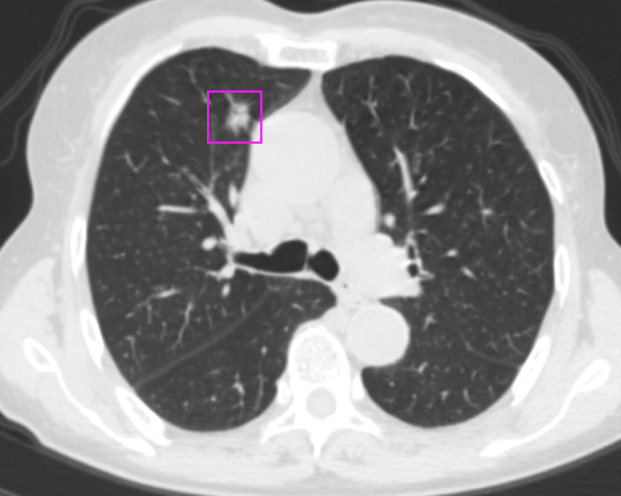

一次感冒,发现双肺结节 患者李女士:“我是由于一次感冒,在老家拍摄胸部CT后发现有双肺结节,后来在家人的陪同下来到市第二人民医院就诊。经过王述波主任团队的手术治疗,顺利地切除了结节,不再担惊受怕了。” 在发现肺结节1个月后,李女士被王述波主任手术团队接诊。团队进行评估发现,该患者CT提示右肺上叶毛刺状结节、左肺上叶混合密度结节,考虑早期肺肿瘤可能性大。(右肺上叶前段结节;左肺上叶上舌段结节) “量体裁衣“精准手术,术后4天康复出院 王述波、王永明主任团队在胸外手术规划系统的指导下,经过术前评估和讨论,决定采取分阶段的手术方案以最大程度地确保手术的成功和患者的安全。 首先,对患者右肺上叶前段采用肺段切除手术进行优先处理。利用系统提供的精准定位功能,准确识别结节周围的血管位置、安全切除范围。术中,在胸腔镜下准确裁剪,保证切缘,确认切除了患者右肺上叶前段肺组织。 最终这例手术过程顺利,术后患者4天康复出院,没有不良反应。(右肺上叶前段病灶阻断血管三维重建图) AI+3D助力手术,消除患者后顾之忧 潍坊市第二人民医院(潍坊呼吸病医院)2024年初引进的3D手术规划系统,为每位患者量身定制了精准的手术方案,在AI+三维重建技术的加持下,为实现精准的肺段及肺亚段切除提供了强有力的支持,达到“量体裁衣”的目的。在术前患者能够清晰了解治疗过程,解除了早期肺癌可能带来的焦虑感,使得治疗过程更加透明和可信。 健康之路,我们与您同行 潍坊市第二人民医院(潍坊呼吸病医院)胸外科是市级医学重点学科,全科医护人员以学科建设、新技术引进和创新为切入点,加强人才培养和引进,现已形成集医疗、教学、科研于一体,具有明显特色和优势的学科。近年来,胸外科开展了气管支气管成形术,肺、食管联合切除手术、单孔胸腔镜肺叶切除、单孔胸腔镜肺段切除、胸腔镜下袖式切除、人工胸骨移植手术、食管癌二切口、三切口,二、三野淋巴清扫等一系列高难度手术,居国内领先水平。由胸外科领衔的肿瘤综合治疗会诊制度,涉及到胸外、呼吸、肿瘤内科、放疗科、放射科等多个专业,对每一位胸部肿瘤患者就诊断、鉴别诊断、治疗及预后等方面进行多学科会诊,受到了全市乃至全省专业同行的认可。咨询电话:0536—8214091/8214109 科普链接 胸腔镜下肺段切除术胸腔镜下肺段切除术,又称胸腔镜下解剖性肺段切除术,采用微创方式将小病变所在的肺段精准切除,在保证肿瘤手术根治的同时,最大限度保留了正常的肺组织,降低了肺功能的损失,实现了真正意义上的微创。